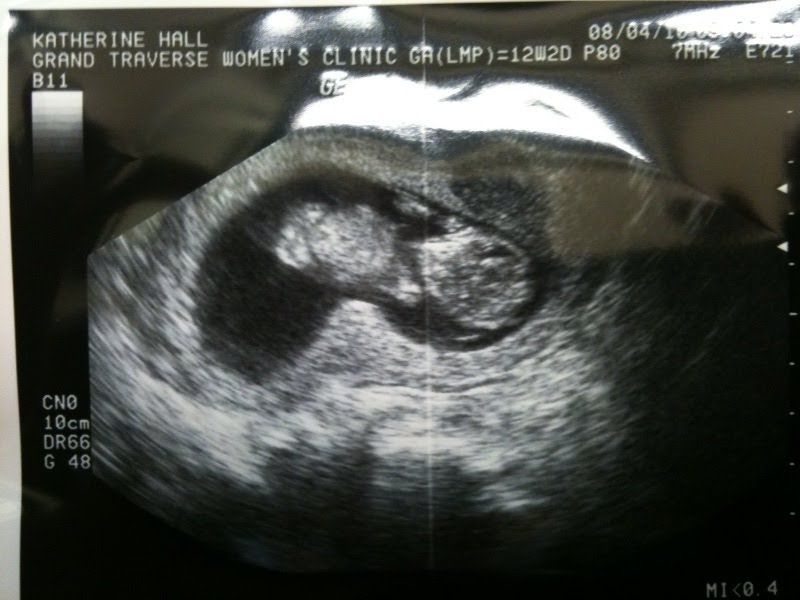

Hi Friends & Family! The word is out...coming February 14th, 2011 Brian and I will welcome a little one into our lives!

Above, is a picture of little Hall! We had our first appointment and ultrasound. Baby Hall looks happy and healthy and was kicking the whole time! In the picture above the baby is sitting Indian style (left) with it's belly (middle), arms by its face and head (right)!

The gender of baby Hall will be a surprise to us & everyone until February but Brian and I both have our guesses..so we shall see!